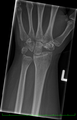

Left hand x-ray with Kienbock's Disease showing 4 mm negative ulnar variance and Kienbock's Disease Stage IIIB